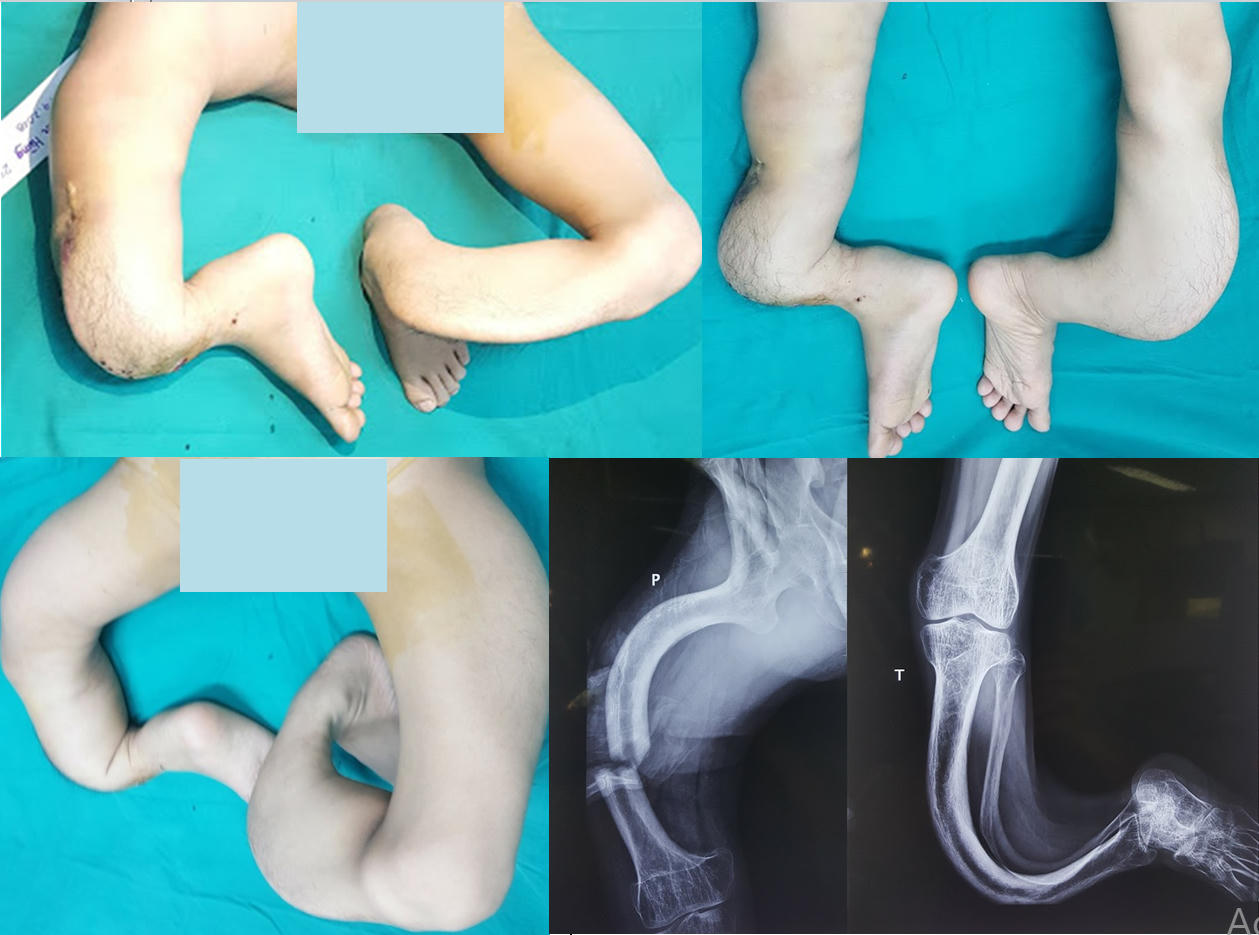

Từ khi lọt lòng, Hùng đã có một đôi chân khác biệt với mọi người. Càng lớn, đôi chân của Hùng càng bị uốn cong, trở nên méo mó vẹo vọ, như "rễ cây". Hùng phải di chuyển và đi lại giống như một con ếch, với hai tay là "bánh lái" và toàn thân dịch chuyển theo "bánh lái" ấy.

Các bác sĩ chuyên ngành của Bệnh viện Trung ương quân đội 108 kinh ngạc trước đôi chân dị dạng của nam bệnh nhân. "Hơn 30 năm làm nghề, tôi chưa bao giờ nhìn thấy một dị dạng phức tạp đến kỳ lạ như thế", Đại tá, GS.TSKH.TTND Nguyễn Thế Hoàng, Phó Giám đốc Bệnh viện TWQĐ108 chia sẻ. "Hình ảnh X-quang cả hai chi dưới cho thấy toàn bộ hệ thống xương khớp ở vùng đùi, cẳng chân và bàn chân đều bị biến dạng cong vẹo và phức tạp theo nhiều chiều, nhiều hướng khác nhau. Chiều dài xương hai bên là hoàn toàn khác biệt. Các cấu trúc phần mềm quan trọng để che phủ, nuôi dưỡng và bảo đảm hoạt động chức năng cho cả hai chân như: da, cân, cơ, gân, mạch máu và thần kinh cũng bị thay đổi hoàn toàn và tạo nên tình trạng chỗ căng chỗ chùng. Do không đi lại tỳ nén nên xương bị thưa loãng nặng".

Cũng theo GS.TSKH.TTND Nguyễn Thế Hoàng, nếu việc điều trị không tốt, sẽ có nguy cơ rối loạn nuôi dưỡng và việc bệnh nhân phải cắt bỏ cả hai chi là không thể tránh khỏi. Ngoài ra, dù có chỉnh thẳng được đi nữa thì theo đo đạc trên phim XQ, chênh lệch của hai chân sẽ là trên 20cm. Với chênh lệch này, bệnh nhân cũng sẽ không thể đi lại bình thường.